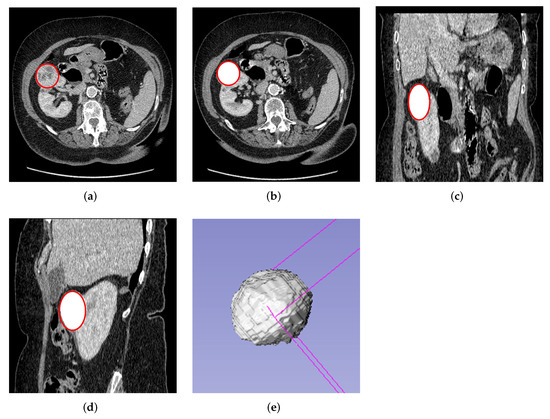

2.4. Segmentation

De-identified DICOM image slices from cohort 1 were converted to 2D JPG format resulting in 967 slices. In addition, the DICOM image slices were also converted to 3D NIFTI format for each patient using Python software for 3D tumor segmentation. Segmentation of the 2D slices was done manually by contracting the edges of the tumor by about 2 mm and delineating the region of interest (ROI). This was done after image grey level conversion and a Wiener filter with kernel size 2 × 2 had been applied using MATLAB software version 9.10. A Wiener filter is a filtering technique used to reduce noise and for image reconstruction to improve medical image quality. Khudayer Jadwa et al. [44] proposed a Wiener filter-based noise reduction method as an effective approach to enhance the image quality from CT and Magnetic Resonance Imaging (MRI) [45]. The 2D segmentation was carried out as shown in Figure 1.

Figure 1. Manual 2D slice image segmentation using image segmentation toolbox in Matlab. (a) Original image with ROI. (b) Segmented tumor from the kidney. (c) Resulting mask from the 2D tumor.